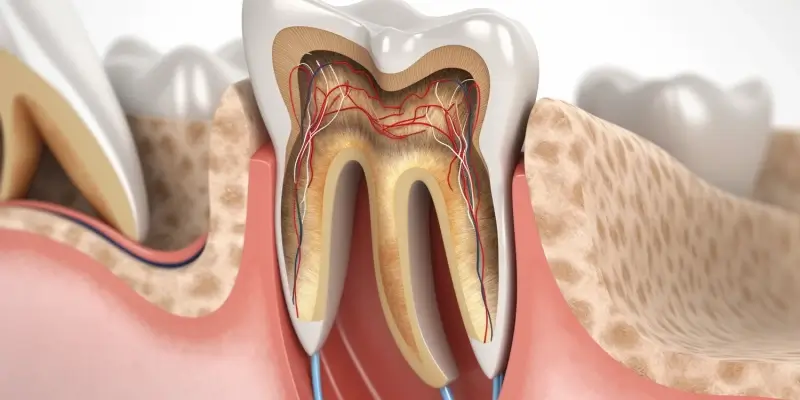

Najlepsze gabinety endodontyczne w Szczecinie oferują szeroki zakres usług, które są dostosowane do indywidualnych potrzeb pacjentów. Podstawowym zabiegiem wykonywanym przez endodontów jest leczenie kanałowe, które ma na celu uratowanie zęba przed ekstrakcją. Specjaliści zajmują się również diagnostyką chorób miazgi zębowej oraz przeprowadzają zabiegi rewizji kanałów korzeniowych w przypadku wcześniejszych niepowodzeń leczenia. Wiele gabinetów oferuje także usługi związane z regeneracją tkanek okołowierzchołkowych oraz leczeniem stanów zapalnych. Nowoczesne technologie, takie jak mikroskopy endodontyczne czy systemy do cyfrowego obrazowania, pozwalają na dokładniejszą diagnozę oraz skuteczniejsze leczenie. Ponadto niektóre gabinety proponują dodatkowe usługi, takie jak konsultacje dotyczące profilaktyki chorób zębów i dziąseł czy porady dotyczące higieny jamy ustnej.

Nowoczesna endodoncja w Szczecinie korzysta z zaawansowanych technologii, które znacząco poprawiają jakość leczenia oraz komfort pacjentów. Jednym z najważniejszych narzędzi jest mikroskop endodontyczny, który pozwala lekarzowi na dokładne zobaczenie struktury kanałów korzeniowych oraz wszelkich anomalii, które mogą występować w ich budowie. Dzięki temu możliwe jest precyzyjne oczyszczenie i wypełnienie kanałów, co zwiększa szansę na powodzenie leczenia. Kolejną innowacją są systemy do cyfrowego obrazowania, takie jak radiografia cyfrowa, która umożliwia uzyskanie wyraźnych zdjęć rentgenowskich przy znacznie mniejszej dawce promieniowania niż tradycyjne metody. To nie tylko zwiększa bezpieczeństwo pacjentów, ale także pozwala na szybsze postawienie diagnozy. Warto również wspomnieć o technologiach laserowych, które są coraz częściej wykorzystywane w endodoncji. Lasery mogą być stosowane do dezynfekcji kanałów korzeniowych oraz usuwania tkanki zapalnej, co przyspiesza proces gojenia i zmniejsza dyskomfort po zabiegu.